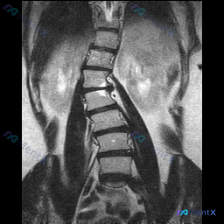

整理到一份腰椎MRI T2冠状位的影像资料,大家先看一眼:

核心影像表现:

- 腰椎明显向左侧弯曲,呈“C”型,顶点在腰椎中部

- 椎体形态基本完整,未见明确骨质破坏或压缩

- 椎间盘T2信号普遍减低(偏暗),提示脱水退变

- 侧弯节段椎间隙左右不对称:右侧张开,左侧闭合

- 两侧旁椎肌肉(腰大肌、竖脊肌)明显不对称

目前给出的分析里最倾向退变性侧弯,但也提到了几个高风险漏诊项。